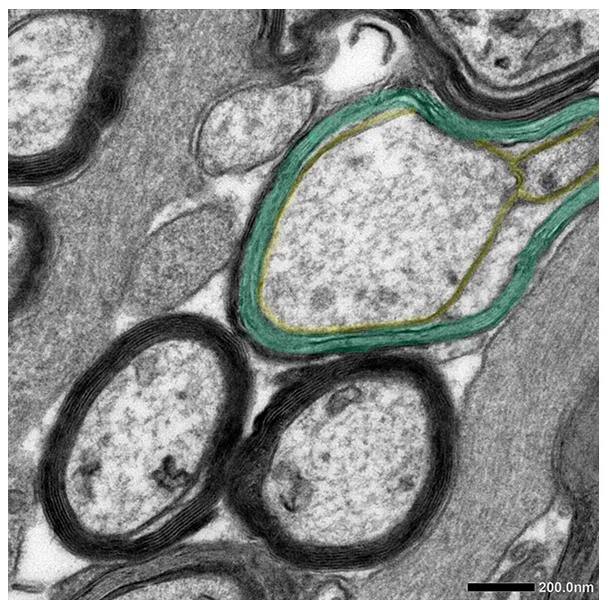

Dioprotectrome™ treated

Repair of coating around nerve fibres

(remyelination) and neurological recovery

Repair of coating around nerve fibres(remyelination) and neurological recovery